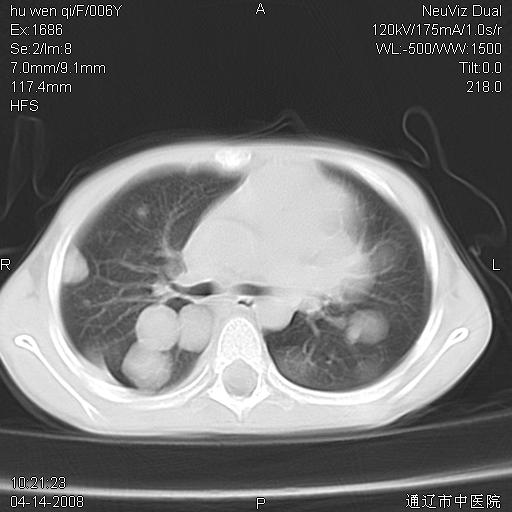

女, 6岁 ,反复咳嗽2周,近两日发热伴右侧胸痛

两肺多发结节状高密度阴影,边界清楚,部分见薄壁空洞,双侧叶间包裹积液;脾大。可能诊断:1、机遇性感染,肺努卡氏菌病;2、血源性葡萄球肺炎

1)考虑为:金黄色葡萄球菌肺炎;不排除两肺多发性转移瘤。2)左上腹(膈下)占位性病变;鉴别于脓肿与肿瘤之间。

左肺下叶肿块伴双肺多发大小不一结节。考虑血源性金黄色葡萄球肺炎。

谢谢各位的诊断意见,结果已经出来了,是神经母细胞瘤肺转移,原发病灶在肾,现在已进行放、化疗。